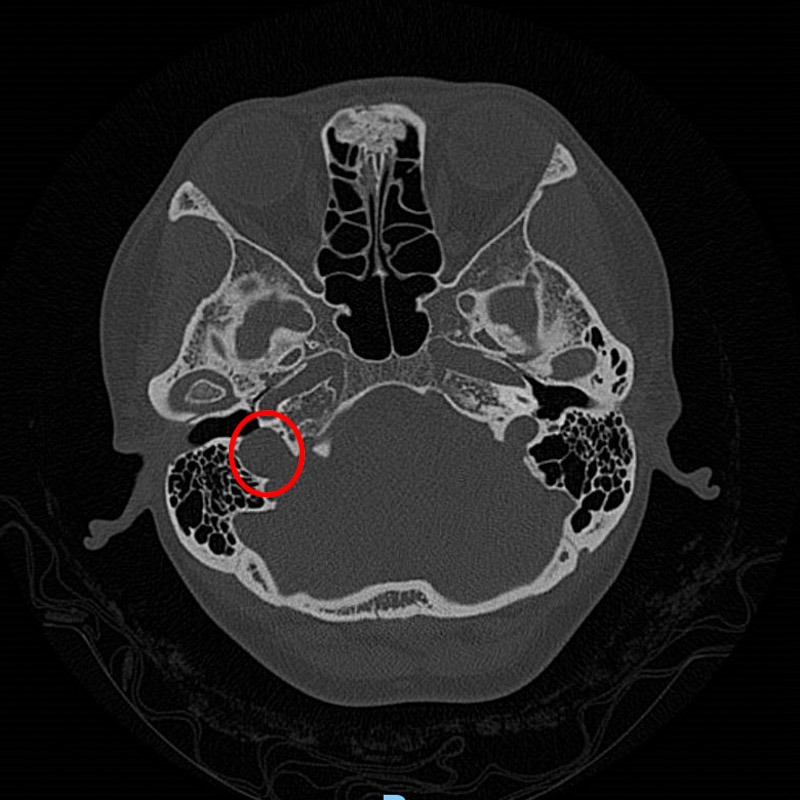

接診醫(yī)生了解情況后,為韋女士做了耳內(nèi)鏡及聽(tīng)力學(xué)檢查,并沒(méi)發(fā)現(xiàn)異常,但根據(jù)患者的實(shí)際情況并結(jié)合多年的經(jīng)驗(yàn)判斷,患者的右耳有可能患有血管搏動(dòng)性耳鳴。為了進(jìn)一步證實(shí),患者進(jìn)行了高分辨頭顱CT檢查,果不其然,放射科醫(yī)生在CT影像學(xué)中發(fā)現(xiàn)了蛛絲馬跡:患者的右側(cè)頸靜脈球高位,可疑合并前壁和外側(cè)壁缺損。這就是導(dǎo)致韋女士耳鳴的罪魁禍?zhǔn)祝?/span>

搏動(dòng)性耳鳴是一種有節(jié)律的耳鳴,由患者頭頸部血管或肌肉產(chǎn)生,并通過(guò)骨骼/血管和血流傳導(dǎo)至耳蝸而感知,患者自述耳內(nèi)有如同心臟或血管脈搏跳動(dòng)頻率一致的耳鳴聲。搏動(dòng)性耳鳴的病因較多,多與血管相關(guān),臨床上頸靜脈球高位為較常見(jiàn)的病因之一。耳部結(jié)構(gòu)復(fù)雜、精細(xì),放射學(xué)醫(yī)師需要豐富臨床經(jīng)驗(yàn)及扎實(shí)的亞專(zhuān)業(yè)知識(shí),才能從影像學(xué)資料中找出耳部細(xì)微的病變部位和病變類(lèi)型。柳州市人民醫(yī)院放射科通過(guò)多年亞專(zhuān)科外派進(jìn)修及與臨床專(zhuān)科密切溝通,對(duì)類(lèi)似專(zhuān)科疾病的確診率大幅度提高,自年初至今發(fā)現(xiàn)類(lèi)似病例10余例,成功實(shí)施手術(shù)治療6例,術(shù)后均取得了較好的療效。